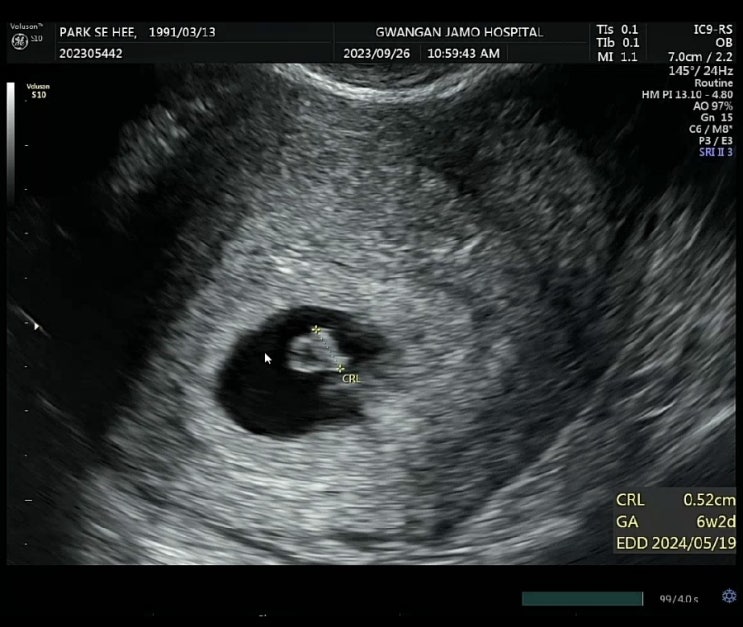

[임신극초기 6,7주차]선홍빛 피비침,병원 입원, 유산방지주사, 임신물혹

임신이 처음이라... 산부인과 의사샘이 많이 걷지말라고 충고를 하였는데.. 별 생각이 없이 이틀연속 팔천...

[임신극초기 5주차] 초음파검사, 자궁 물혹, 입덧

5,6주차부터 드디어 질초음파로 자그마한 생명을 볼 수 있었당! 너무 자그마해... 난황이 하트모양으로 있...